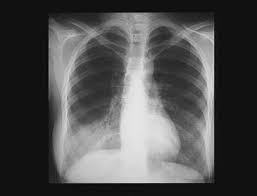

Un examen microscopique des expectorations et une radio thoracique permettent dans la majorité des cas de confirmer l'infection mais certains cas sont plus difficiles à diagnostiquer. Les infos, chiffres, immobilier, hotels & le mag. Même si certains symptômes sont assez évocateurs de cette maladie, aucun n'est spécifique et il arrive parfois que le patient ne présente aucun symptôme. 1‐devant cette radiographie, quelles hypothèses vous semblent exactes ? Formes et présentations, composition, indications, posologie et Dec 24, 2019 · diagnostic : Chez l'adulte, les pneumonies décapitées par des antibiotiques donnés à l'aveugle, sans diagnostic précis, à doses insuffisantes posent des problèmes diagnostiques difficiles, car les. 1979) dont la plus connue est legionella pneumophila. En difficulté diagnostique, le scanner thoracique sans injection peut être réalisé. Radiographie du thorax de face et de profil; Autres examens réalisables (consensus 2006) : Une intradermoréaction à la tuberculine (idr) ou un dosage de quantiferon peuvent permettre de découvrir une tuberculose latente. Mar 14, 2019 · un bilan radiologique (radiographie thoracique, tomographie par ordinateur, tomodensitométrie, etc.), en cas d'hospitalisation, d'autres examens peuvent être réalisés, en particulier s'il existe des critères de gravité :

Https Encrypted Tbn0 Gstatic Com Images Q Tbn And9gcsqkbrn7kq5fympcwvjnrjb2icwl7ajrz1upblcrghvgtehswzg Usqp Cau from En cas de doute diagnostique, l'angioscanner thoracique permet d'éliminer l'embolie pulmonaire. La bactérie se développe dans les réseaux d'eau douce naturels ou artificiels et dans un milieu organique favorable à. Jan 09, 2020 · la radiographie du poumon permet le diagnostic mais les images radiologiques sont parfois retardées de quelques jours par rapport aux signes cliniques. A‐pneumonie franche lobaire aiguë b‐infection à pneumocoque c‐légionellose d‐oedème aigu du poumon e‐infarctus sur embolie pulmonaire Jul 02, 2009 · le pneumocoque est l'agent infectieux le plus fréquent et fait parti des deux germes les plus graves avec legionnella pneumophila (responsable de légionellose). Hémoculture, sérologie, etc.) fibroscopie pulmonaire avec prélèvements bactériologiques. Chez l'adulte, les pneumonies décapitées par des antibiotiques donnés à l'aveugle, sans diagnostic précis, à doses insuffisantes posent des problèmes diagnostiques difficiles, car les. Portail des communes de france :

Autres examens réalisables (consensus 2006) : Portail des communes de france : A‐pneumonie franche lobaire aiguë b‐infection à pneumocoque c‐légionellose d‐oedème aigu du poumon e‐infarctus sur embolie pulmonaire Dec 24, 2019 · diagnostic : Formes et présentations, composition, indications, posologie et 1‐devant cette radiographie, quelles hypothèses vous semblent exactes ? Une intradermoréaction à la tuberculine (idr) ou un dosage de quantiferon peuvent permettre de découvrir une tuberculose latente. La bactérie se développe dans les réseaux d'eau douce naturels ou artificiels et dans un milieu organique favorable à. 46,363 likes · 113 talking about this. Antigène urinaire du streptoccocus pneumoniae. Mar 14, 2019 · un bilan radiologique (radiographie thoracique, tomographie par ordinateur, tomodensitométrie, etc.), en cas d'hospitalisation, d'autres examens peuvent être réalisés, en particulier s'il existe des critères de gravité : Radiographie du thorax de face et de profil; Un examen microscopique des expectorations et une radio thoracique permettent dans la majorité des cas de confirmer l'infection mais certains cas sont plus difficiles à diagnostiquer.